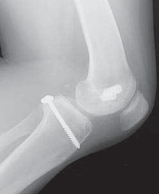

8. Radiographs of the knee should be performed following an acute injury to assess for a fracture. An avulsion of the tibial insertion of the PCL may be identified on a lateral radiograph (

FIG 1A

).

FIG 1 • A. Avulsion fracture of the tibial insertion of the posterior cruciate ligament (PCL). B. Posterior subluxation of the

tibia in a case of chonic PCL deficiency.

1. In the chronic setting, radiographs may identify posterior tibial subluxation (

FIG 1B

) or medial and patellofemoral compartmental arthrosis.